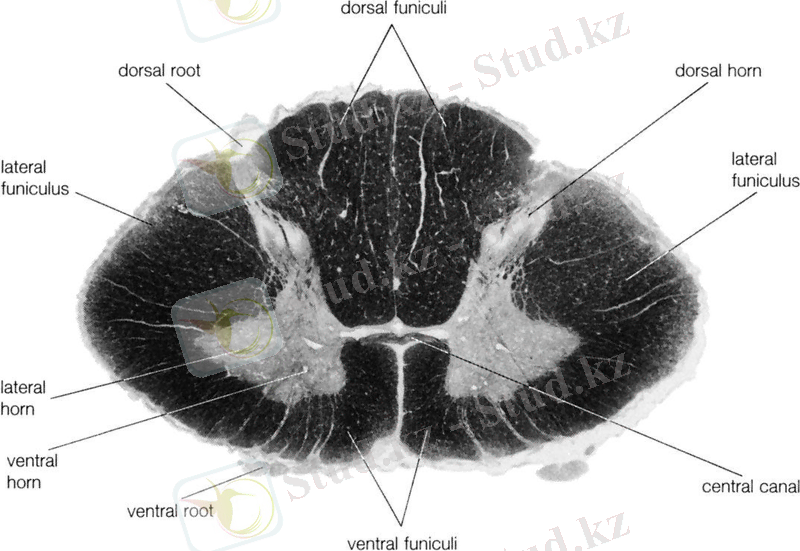

Сурет 1. Жұлынның көлденең кесіндісі.